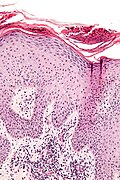

Micro

The sections show hair bearing skin with solar elastosis and numerous small dilated blood vessels. The dermis is mildly fibrotic. Compact keratin is present.

The epidermis matures to the surface. A granular layer is present. There is no basal epidermal atypia. No melanocytic nests are identified. There is no palisading of the basal cells. Rare scattered lymphocytes are in the dermis.